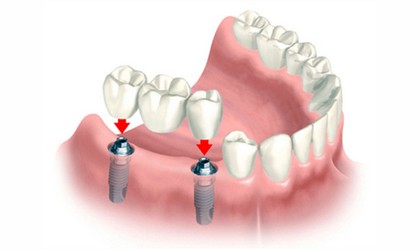

İmplant diş eksikliklerinde üzerine protez yapmak için kullanılan titanyum vida sistemidir. Çene kemiğine yerleştirilen implantlar diş kökü gibi görev yaparlar. Tek diş eksikliklerinde, komşu sağlam dişlere dokunulmadan eksik dişi tamamlamak mümkün olabildiği gibi çoklu diş eksikliklerinde hareketli protez yerine sabit protezler kullanabilmek implantlar sayesinde mümkündür.

Özellikle uzun yıllardır dişsiz olan hastaların mevcut protezleri kemikte değişim devam ettiğinden dolayı zamanla uyumunu kaybederek hareket etmeye, vuruklara neden olmaya başlar. İmplant üstüne yapılan protezler sabit bir temelin üstüne yapıldığı için hareket etme veya ağızdan çıkma özelliği bulunmamaktadır. Hareketli protez istemeyen veya kemiğin tutuculuğunu kaybettiği kişilerde uygulanabilir.